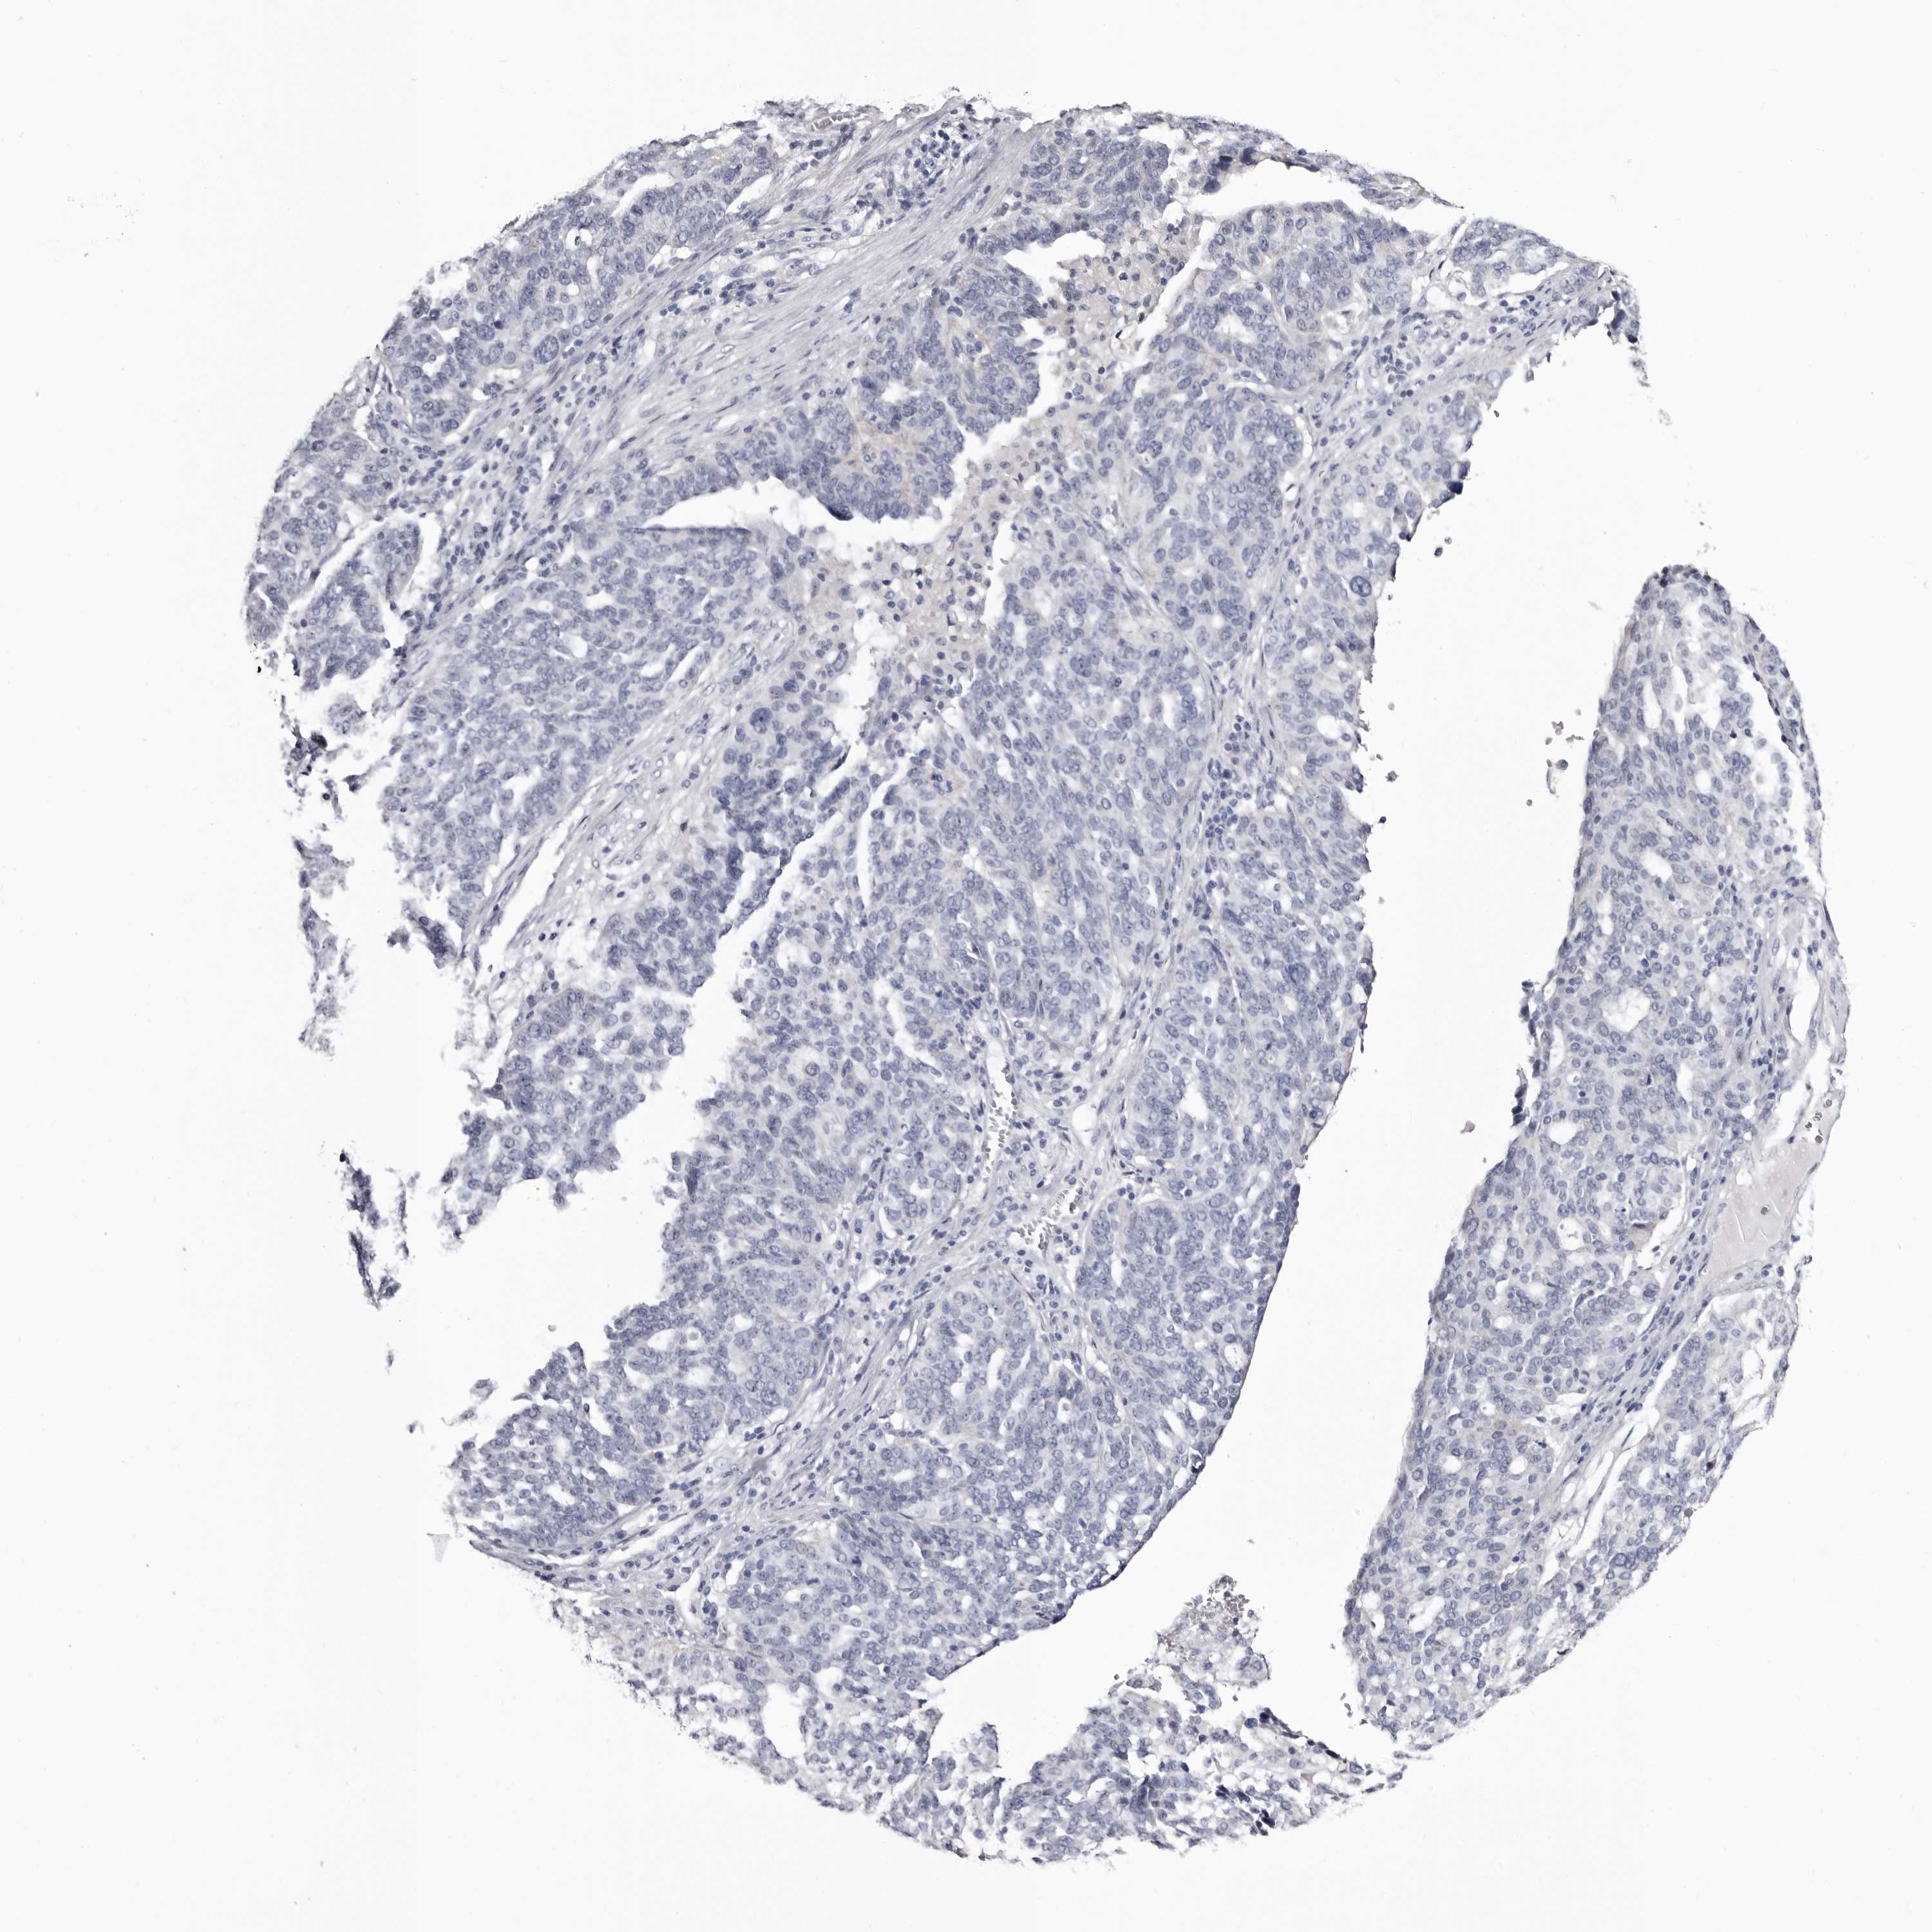

OVARIAN CANCER - Protein expressioni

A mouse-over function shows sample information and annotation data. Click on an image to view it in a full screen mode. Samples can be filtered based on level of antibody staining by selecting one or several of the following categories: high, medium, low and not detected. The assay and annotation is described here.

Note that samples used for immunohistochemistry by the Human Protein Atlas do not correspond to samples in the TCGA dataset.

Antibody stainingi

Antibody staining in the annotated cell types in the current human tissue is reported as not detected, low, medium, or high, based on conventional immunohistochemistry profiling in selected tissues. This score is based on the combination of the staining intensity and fraction of stained cells.

Each image is clickable and will lead to virtual microscopy that enables deeper exploration of all samples and also displays staining intensity scores, fraction scores and subcellular localization as well as patient and tissue information for each sample.

Antibody HPA007845

Antibody HPA026823

Antibody CAB015170

Cystadenocarcinoma, serous, NOS

Carcinoma, endometroid

Cystadenocarcinoma, mucinous, NOS

Carcinoma, NOS